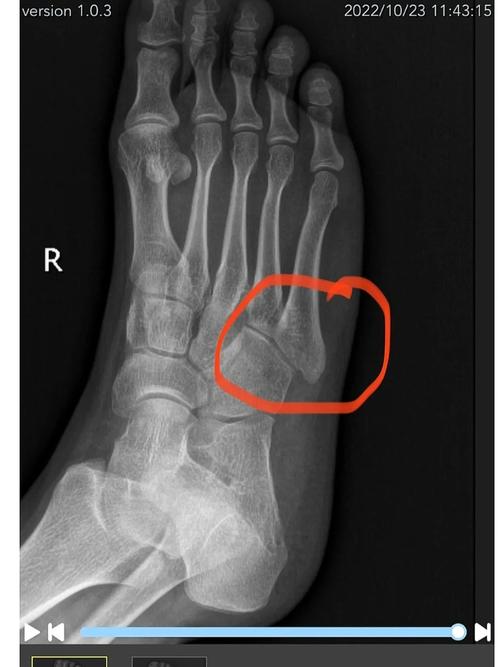

我最近脚骨折了,正打算做试管婴儿,特别担心脚骨折这个情况会不会降低我做试管婴儿的成功率呀?是会影响卵子质量还是胚胎着床,亦或是在其他方面对成功率产生不好的作用呢?